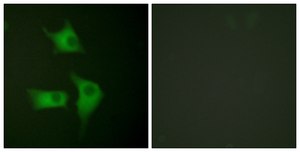

immunofluorescence: 1:100-1:500

Anti-p15 INK Antibody detects endogenous levels of total p15 INK protein.

Cyclin-dependent kinase inhibitor 2B (CDKN2B) gene codes for tumor-suppressor p15INK4B protein. p15INK4B is a member of the INK4 family of protein kinase inhibitors. In bone marrow cells, p15INK4B expression is mainly seen at a high level in maturing monocytes/macrophages and lymphocytes. It is located in the nucleus and cytoplasm. The CDKN2B gene is mapped to human chromosome 9p21.3. Anti-p15 INK Antibody detects endogenous levels of total p15 INK protein.